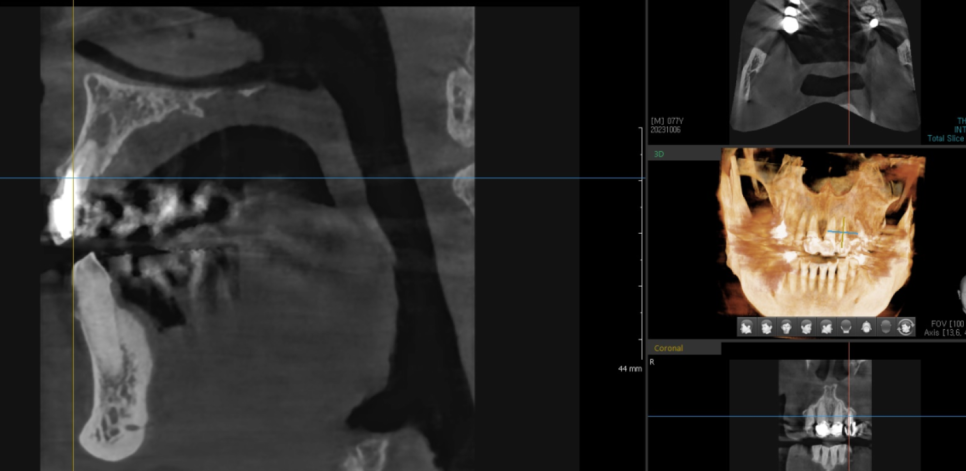

231005

위쪽 앞니 브릿지(#22~24) 부위가

심하게 흔들려서 내원하셨는데요...

검사를 해보니 동요도가 3도

이상인 상태였습니다.

231011

방사선 사진을 확인하니

치아 뿌리 끝에 염증이 크게 번져

주변 잇몸뼈를 많이 녹인 상태였습니다.